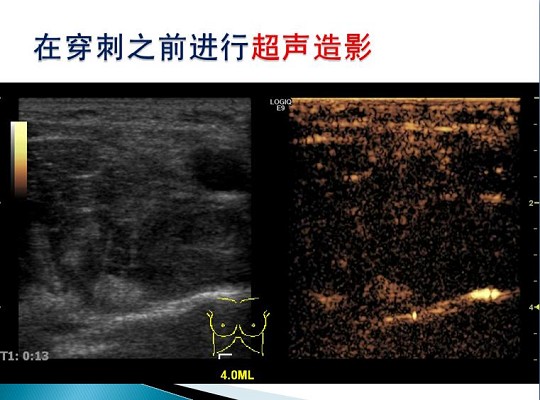

第三届中国超声造影大会病例大赛北医三院超声科获奖病例展示(四)